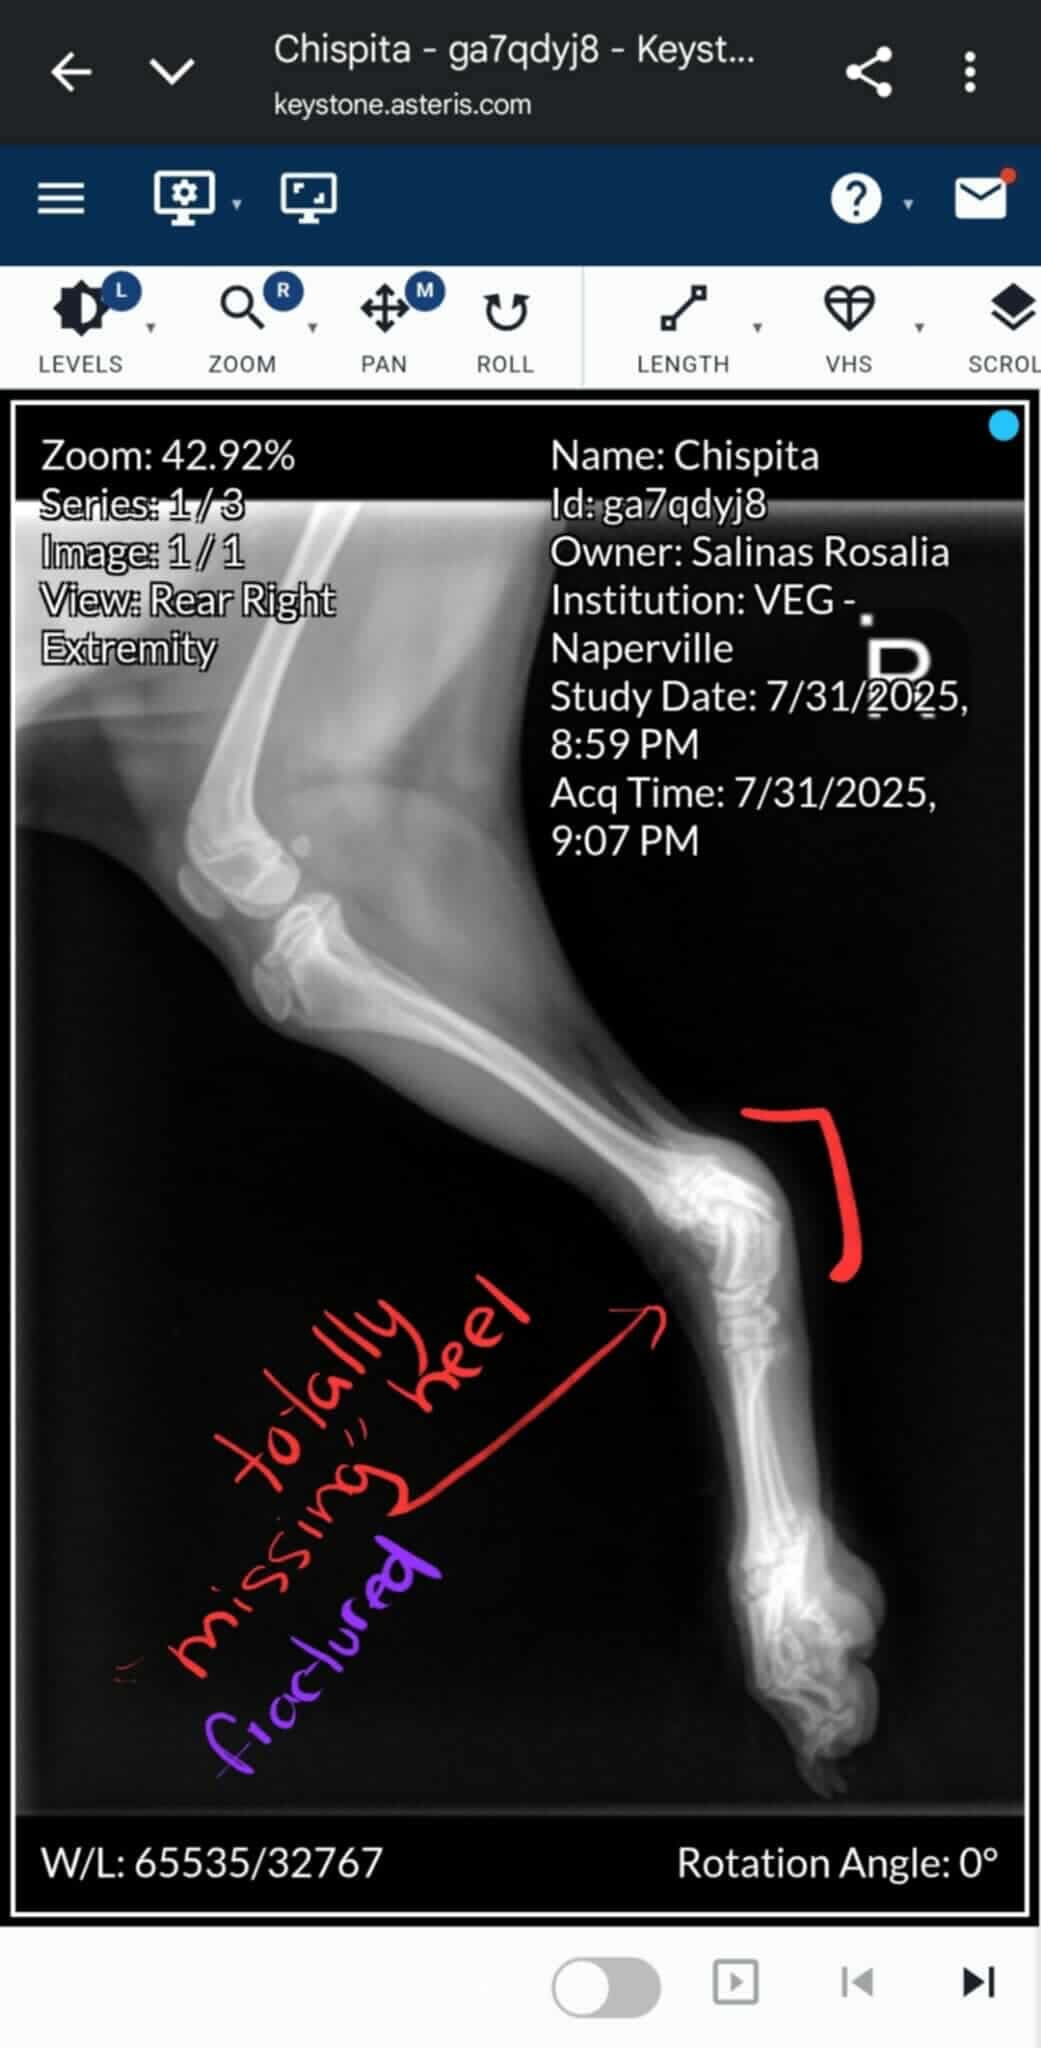

Chispita is my sister’s beloved 6-month-old yorkie mix puppy, and she’s always been a source of joy and comfort for their family. Recently, Chispita suffered a broken heel and now can’t walk or play like she used to. It’s heartbreaking to see her in pain, especially knowing how much she means to my sister and her two young children.

My sister is the only provider for her family. Her partner recently lost his job, and with two kids to care for, covering the cost of Chispita’s urgent surgery is overwhelming. The veterinarians have said that Chispita needs surgery as soon as possible to repair her heel. Without it, she may lose her leg. My sister has already spent a lot on initial exams and treatment, but the surgery and follow-up care are more than she can manage alone right now.

Chispita es la perrita mestiza de yorkie de 6 meses de mi hermana, y siempre ha sido una fuente de alegría y consuelo para su familia. Recientemente, Chispita sufrió una fractura en el talón y ahora no puede caminar ni jugar como antes. Es desgarrador verla con dolor, especialmente sabiendo cuánto significa para mi hermana y sus dos hijos pequeños.

Mi hermana es la única proveedora de su familia. Su pareja perdió recientemente su trabajo y, con dos niños a su cargo, cubrir el costo de la cirugía urgente de Chispita es abrumador. Los veterinarios han dicho que Chispita necesita la cirugía lo antes posible para reparar su talón. Sin ella, podría perder la pierna. Mi hermana ya ha gastado mucho en exámenes y tratamientos iniciales, pero la cirugía y el cuidado posterior son más de lo que puede manejar sola en este momento.